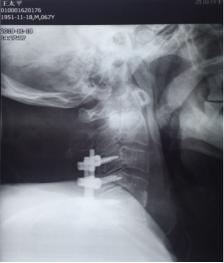

术 后

11月13日行手术治疗,后前路联合手术。先行颈后路切开,颈3-6椎体侧块螺钉固定,再行前路颈4.5间盘以及颈前脓液清理,椎间隙植骨融合术。术中见颈4.5椎间隙前缘被一直径1.5㎝肿物包裹,打开后,可见其内少许米汤样脓性液,肿块壁为脓性物。间盘内充填相同物,上、下缘软骨板漂浮,翘起,上下椎体相邻面骨质酥脆,同时后缘有大量不良增生物,骨钩分离后,可见自颈5椎体后缘,流出同样的米汤样脓液。彻底清理脓性液,充分刮除椎体不良骨质。大量生理盐水冲洗,取三面皮质髂骨块置于椎间隙,敲紧。术后前侧放引流管于脓腔间隙。术后留置3.5天。术中留取的脓液细菌培养仍为阴性,刮出的椎间盘及囊壁病检结果显示为化脓性炎表现。术后继续抗生素治疗,患者体温正常,四肢肌力改善明显,下肢肌力术后第2天恢复至2级。上肢肌力4级弱。躯干部位感觉平面下降至乳头以远,大小便功能改善不明显。